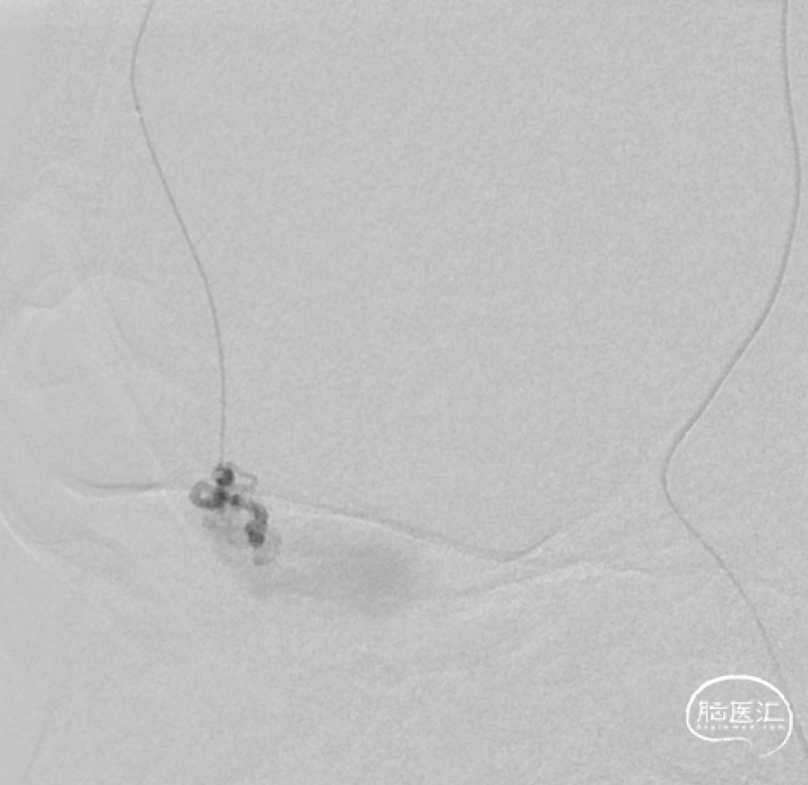

治疗经过

二期治疗